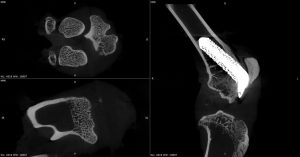

High‑resolution micro-CT enables the non‑destructive, 3D visualization of implants and surrounding bone over time. The images presented here showcase the use of micro-CT to study periprosthetic joint implantation and osseointegration in rabbit models, allowing tracking of implant positioning, bone remodeling, and early indicators of bone integration at multiple time points.

Below are micro-CT reconstructions of a femoral implant in a rabbit knee model. High-resolution imaging enables tracking of implant position and progressive changes at the implant-bone interface over time.

Temporal Assessment of Implant-Bone Interactions

Micro-CT imaging allows repeated scanning of the same implanted joint, providing a powerful means to observe temporal changes in bone architecture without disrupting the tissue. These scans allow monitoring of how the surrounding trabecular and cortical bone adapts to the presence of the implant, capturing subtle changes in bone volume, density, and structure as healing progresses. This approach enables precise comparison of early versus later stages of implant integration within the rabbit knee.